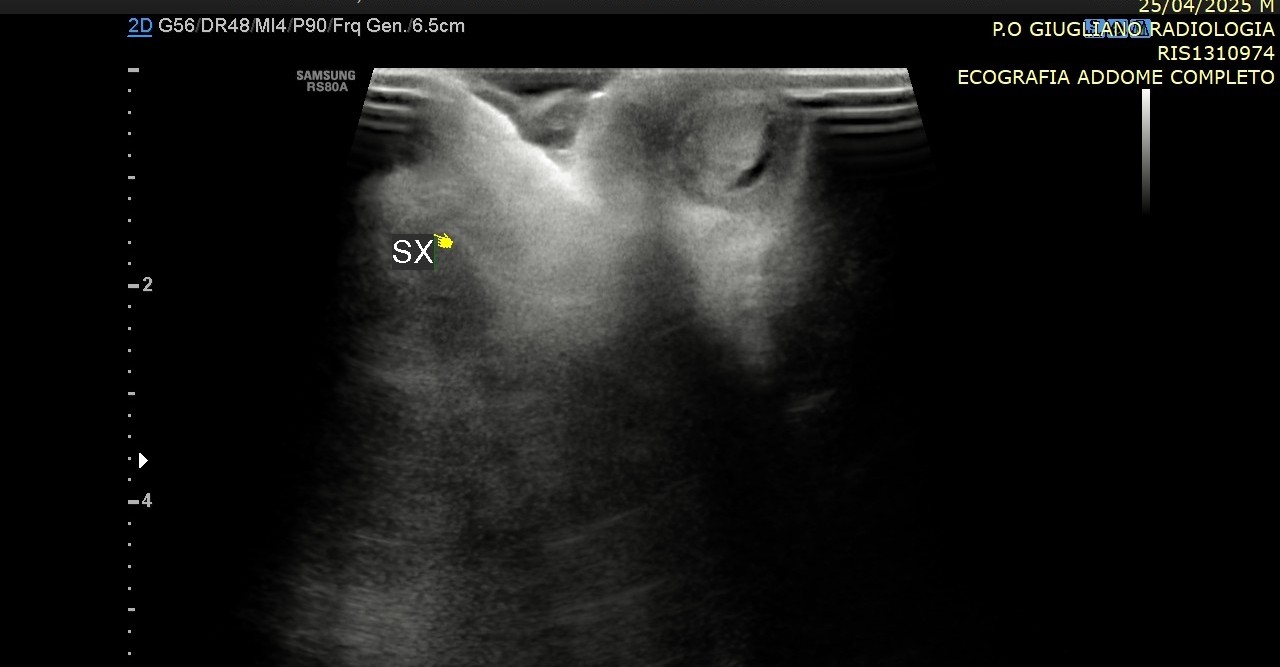

La diagnosi si basa innanzitutto sull’esame obiettivo del neonato o del bambino, affiancato quando necessario da indagini ecografiche o laparoscopiche. Il trattamento di scelta è chirurgico, tramite orchidopessi, e dovrebbe essere eseguito precocemente, idealmente tra i 6 e i 12 mesi di età, per ridurre al minimo i rischi futuri.